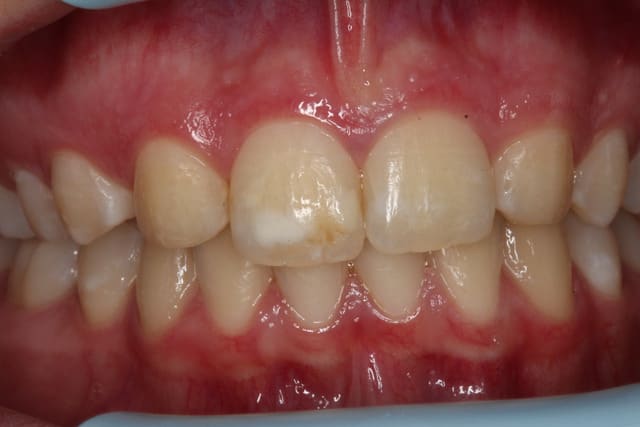

Patiente jeune (16ans) que je dois revoir pour des soins.

Que feriez-vous si elle vous demandait en montrant la tâche blanche sur l'incisive : "est-il possible de faire quelque chose pour çà Docteur ?"

Je ne suis pas chaud pour le composite, encore moins pour la facette. Je pensais à l'ICON de DMG mais j'aimerais vos avis.

Je dirais Icon voire micro-abrasion. la tâche a l'air profonde.

amha Eclaircissement externe général pour uniformiser + ICON